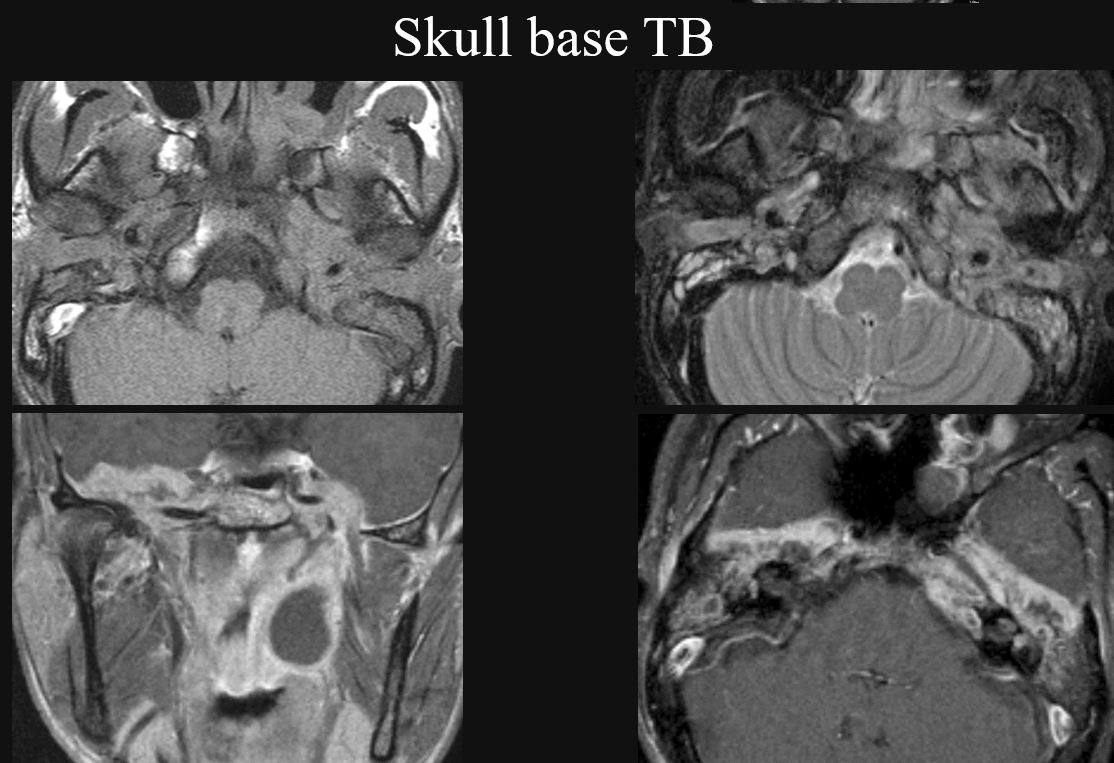

Temporal Bone and Skull Base Osteomyelitis

Skull Base Osteomyelitis

Skull base osteomyelitis (SBO) not related to necrotizing otitis externa (NOE) as described above.